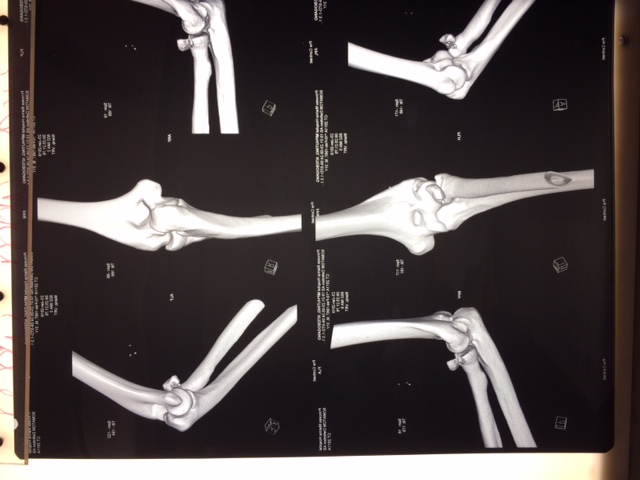

Нужен совет о необходимости хирургического лечения молодого пациента. 2 недели после падения на разогнутую руку. Был в лонгете. Сейчас небольшая боль, движения 20-80 град., пронация и супинация ограничены на 50%. Я склоняюсь в пользу консервативного лечения - продолжить ЛФК, если боль останется , можно позже удалить фрагмент(?- доступ).

Имя     : IMG_3367.JPG

Url     : http://weborto.net:8080/pipermail/ortho/attachments/20190203/d60d8df7/attachment-0001.jpe